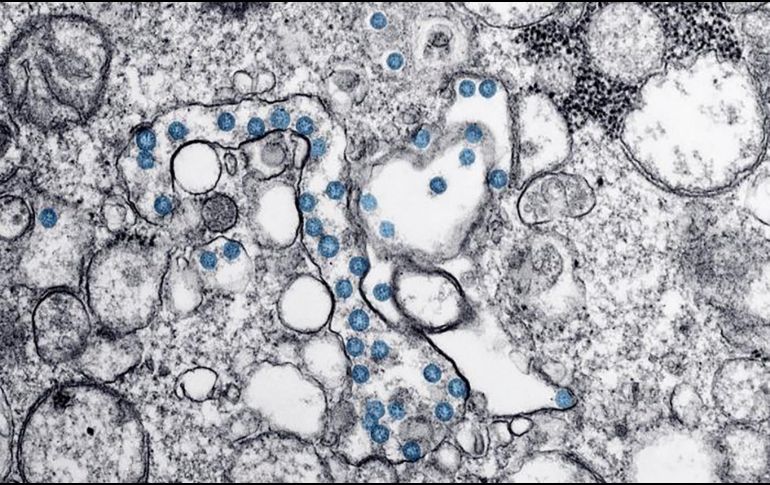

Resaltan que, hasta el momento, todas las variantes que han aparecido no son más letales, sino que cambia la rapidez en la que las personas pueden contagiarse. AFP / ARCHIVO